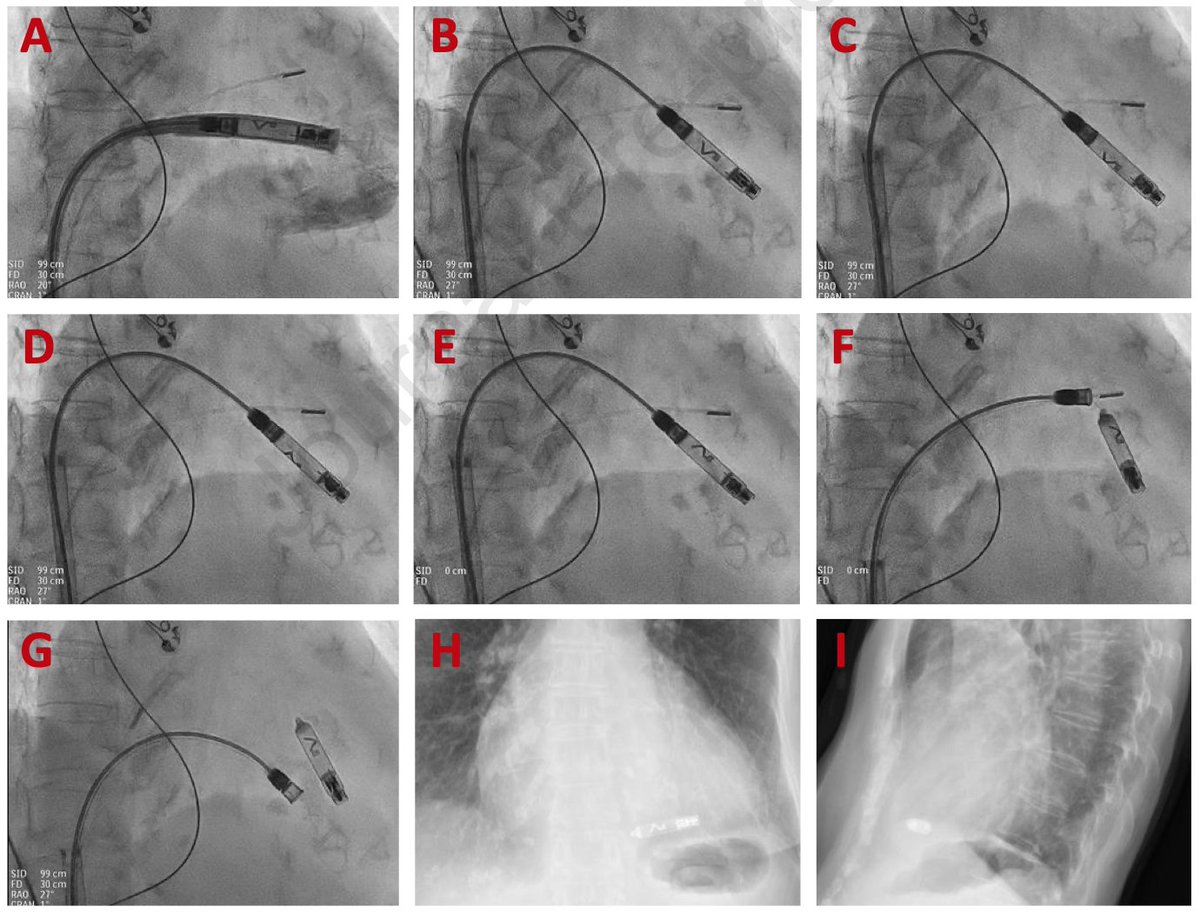

Dual Chamber Aveir from Abbott with ICE-guidance targeting the mouth of the RAA. Love it. Controlled, safe implant. Very exciting option for some patients #EPeeps

Great Aveir day at presby today including an implant on one of the smallest young patients in US to date! Looking forward to the future of pacing!